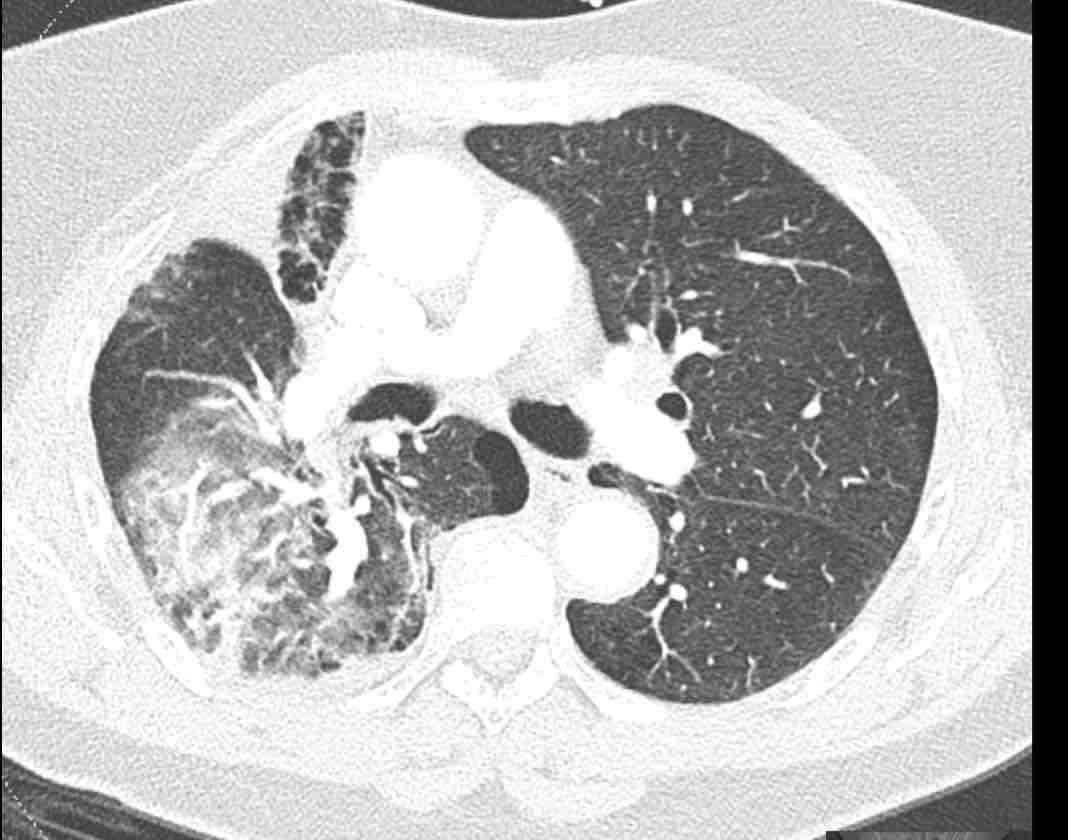

Hình ảnh

Cuộn qua các hình ảnh.

Theo dõi các phế quản của thùy dưới phổi trái cho thấy nhánh phân thùy đầu tiên của thùy dưới phổi trái còn thông; đó là phế quản phân thùy đỉnh.

Các ghim phẫu thuật nằm tại vị trí của các phân thùy đáy sau và đáy bên (LB9/10), vốn thường được cắt bỏ cùng nhau.

Do đó, phân thùy phổi có hình ảnh kính mờ và đông đặc phải là phân thùy đáy trước của thùy dưới phổi trái (LB8).

Động mạch phổi đến phân thùy này cũng không ngấm thuốc cản quang, và bản đồ tưới máu iốt nhấn mạnh thêm tình trạng nhồi máu.

Bệnh nhân đã được phẫu thuật lại và tiến hành cắt bỏ phân thùy bị nhồi máu, với xác nhận qua giải phẫu bệnh.

Tiếp tục với bản đồ tưới máu…

Trên bản đồ tưới máu iốt, có sự tưới máu ở thùy trên phổi trái và phân thùy đỉnh của thùy dưới phổi trái, nhưng không có sự tưới máu ở phân thùy đáy trước của thùy dưới phổi trái.